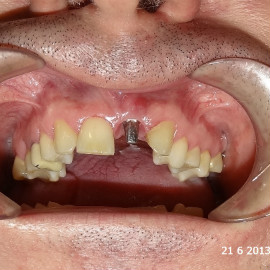

Lat 50, pół roku przed rozpoczęciem leczenia implantologicznego przestał palić papierosy. Znacząca poprawa higieny, pacjent silnie zmotywowany. Po regeneracji kości i rekonstrukcji tkanek miękkich odbudowa sześciu zębów na koronach porcelanowych. Na zdjęciu widoczna ilość i jakość tkanki kostnej po rekonstrukcji. W porównaniu ze stanem początkowym uzyskano znaczącą poprawę warunków kostnych nie do osiągnięcia metodami sterowanej regeneracji kości z użyciem reklamowanych markowych błon kolagenowych i dosypaniem kości z butelki.